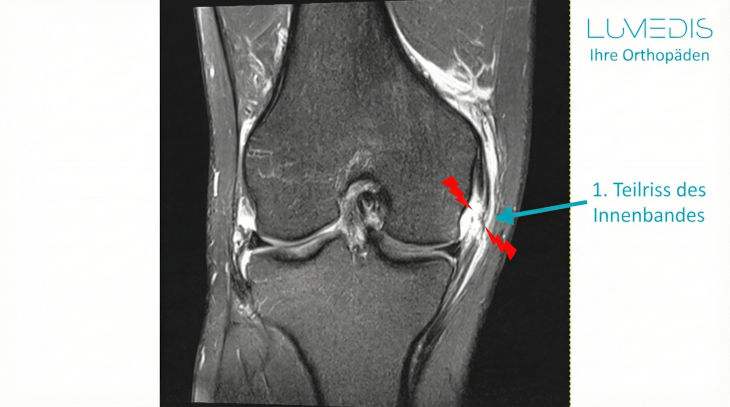

MRT eines Innenbandrisses am Kniegelenk (T2 ap)

Abbildung Innenbandriss / Innenbandteilriss Knie

MRT eines angerissenen Innenbandes